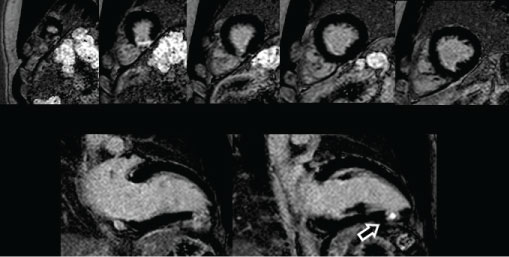

In a second visit, a multislice computed coronary tomography (MSCT) was performed and revealed multiple pulmonary CF from the septal branch of the left anterior descending artery (LADA) and right coronary artery (RCA) (Figure 2). Suspecting associated myocardial infarction, a cardiac magnetic resonance was requested and showed late gadolinium enhancement in inferoapical segments, with necrotic ischemic pattern and transmural extension (Figure 3). For treatment planning a coronary angiography was performed to evaluate CF morphology, observing a Sakakibara A complex and tortuous macrofistula emerging from the proximal segment of LADA with a common stem and 2 branches of 2 mm diameter each one, and a Sakakibara A macrofistula of 2mm diameter from the proximal segment of RCA, both draining into the pulmonary artery.

Figure 3: Cardiac magnetic resonance (T1-weighted gradient echo acquisition). Short and long axis views. Late gadolinium enhancement in inferoapical segments, with necrotic ischemic pattern and transmural extension (white arrows). View Figure 3